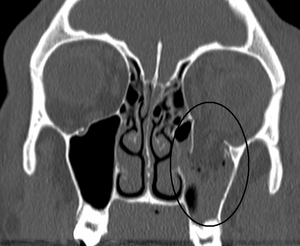

Orbital blowout fracture

| An orbital blowout fracture of the floor of the left orbit. | |

An orbital blowout fracture is a traumatic deformity of the orbital floor or medial wall, typically resulting from impact of a blunt object larger than the orbital aperture, or eye socket. There are two broad categories of blowout fractures: open door, which are large, displaced and comminuted, and trapdoor, which are linear, hinged, and minimally displaced. They are characterized by double vision, sunken ocular globes, and loss of sensation of the cheek and upper gums due to infraorbital nerve injury.[1]

In pure orbital blowout fractures, the orbital rim (the most anterior bony margin of the orbit) is preserved, while with impure fractures, the orbital rim is also injured. With the trapdoor variant, there is a high frequency of extra-ocular muscle entrapment, despite minimal signs of external trauma, a phenomenon referred to as a 'white-eyed' orbital blowout fracture.[2] They can occur with other injuries such as transfacial Le Fort fractures or zygomaticomaxillary complex fractures. The most common causes are assault and motor vehicle accidents. In children, the trapdoor subtype are more common.[3] Reconstruction is usually performed with a titanium mesh or porous polyethylene through a transconjunctival or subciliary incision. More recently, there has been success with endoscopic, or minimally invasive, approaches.[4]